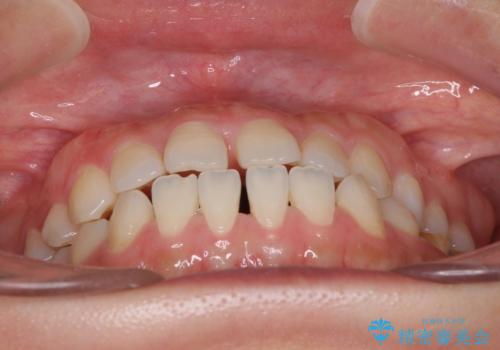

- 上下の前歯の隙間を気にして来院された患者様です。

インビザラインを用い、上下歯列のスペースを閉じていくこととしました。